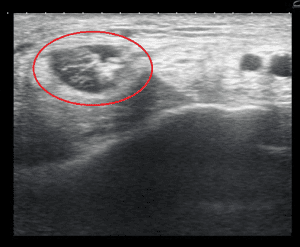

Ultrasound examination at The Foot and Ankle Centre can assist in diagnosing this problem. Below shows the position of the probe and the findings in posterior tibial tendon degeneration.

Probe positionNote the fluid surrounding the tendonFibres of the tendon are discontinuous